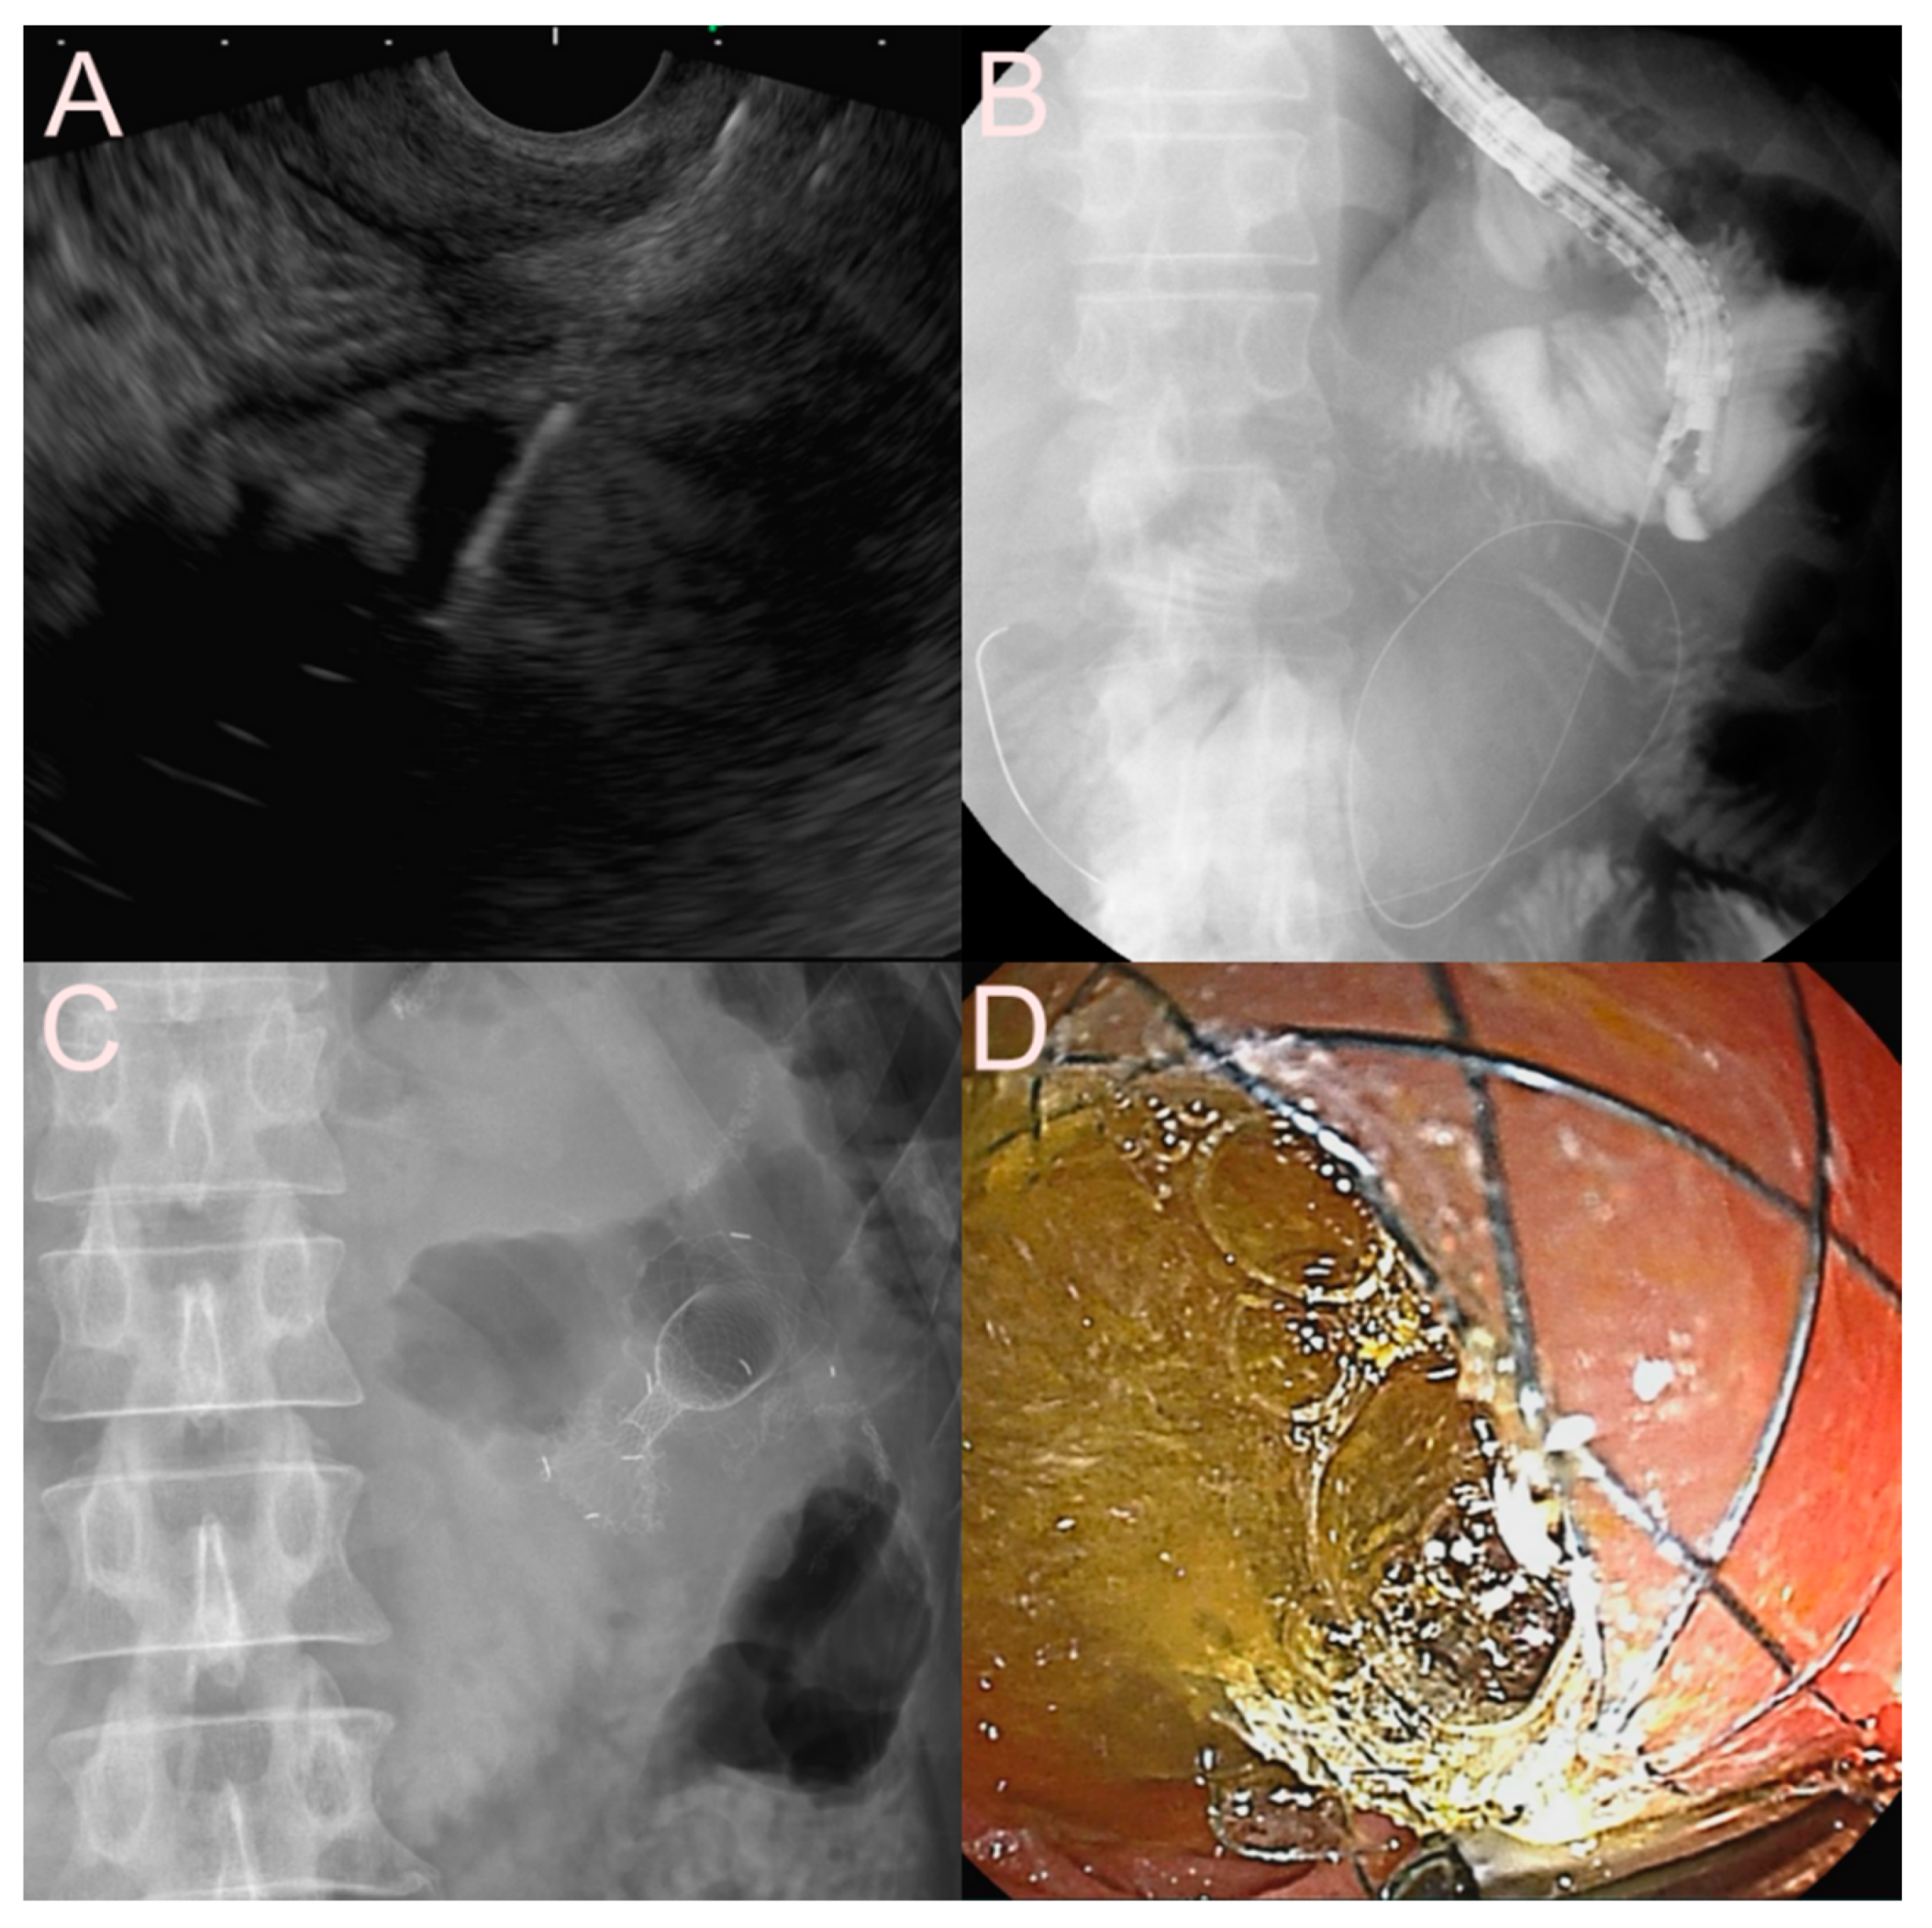

2.3.3. Use of the LAMS